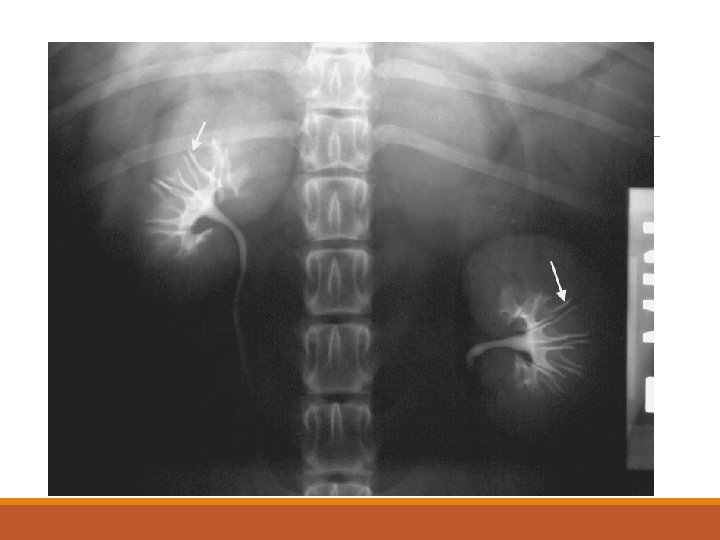

Contrast Studies for the Urinary Tract Excretory Urography (EU) – Intravenous Pyelogram (IVP) – Intravenous Urography (IVU) ◦ Indications ◦ Evaluate kidney morphology – position. Ureters. ◦ Suspected renal disease ◦ Increased radiopacity in the retroperitoneal space ◦ Gross idea of kidney function ◦ Procedure ◦ Preparation required (24 h fasting; enema) ◦ IV access/dose ◦ Radiographic views

Excretory Urography (EU) – Intravenous Pyelogram (cont’d) ◦ Interpretation ◦ Vascular phase Ø 5 – 10 sec ◦ Nephrogram phase Ø 1 – 2 min ØNormal pattern: Initial=Good, then=gradual decrease ØAbnormal patterns: ØPoor – persistent ØPoor – continued increase/ decrease ØGood – continued increase